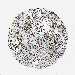

PANCREATIC CANCER - Protein expressioni

A mouse-over function shows sample information and annotation data. Click on an image to view it in a full screen mode. Samples can be filtered based on level of antibody staining by selecting one or several of the following categories: high, medium, low and not detected. The assay and annotation is described here.

Note that samples used for immunohistochemistry by the Human Protein Atlas do not correspond to samples in the TCGA dataset.

Antibody stainingi

Antibody staining in the annotated cell types in the current human tissue is reported as not detected, low, medium, or high, based on conventional immunohistochemistry profiling in selected tissues. This score is based on the combination of the staining intensity and fraction of stained cells.

Each image is clickable and will lead to virtual microscopy that enables deeper exploration of all samples and also displays staining intensity scores, fraction scores and subcellular localization as well as patient and tissue information for each sample.

Antibody CAB012342

Staining

High

Medium

Low

Not detected

Intensity

Strong

Moderate

Weak

Negative

Quantity

>75%

75%-25%

<25%

None

Location

Nuclear

Cytoplasmic/membranous

Cytoplasmic/membranous,nuclear

Adenocarcinoma, NOS

Adenocarcinoma, metastatic, NOS